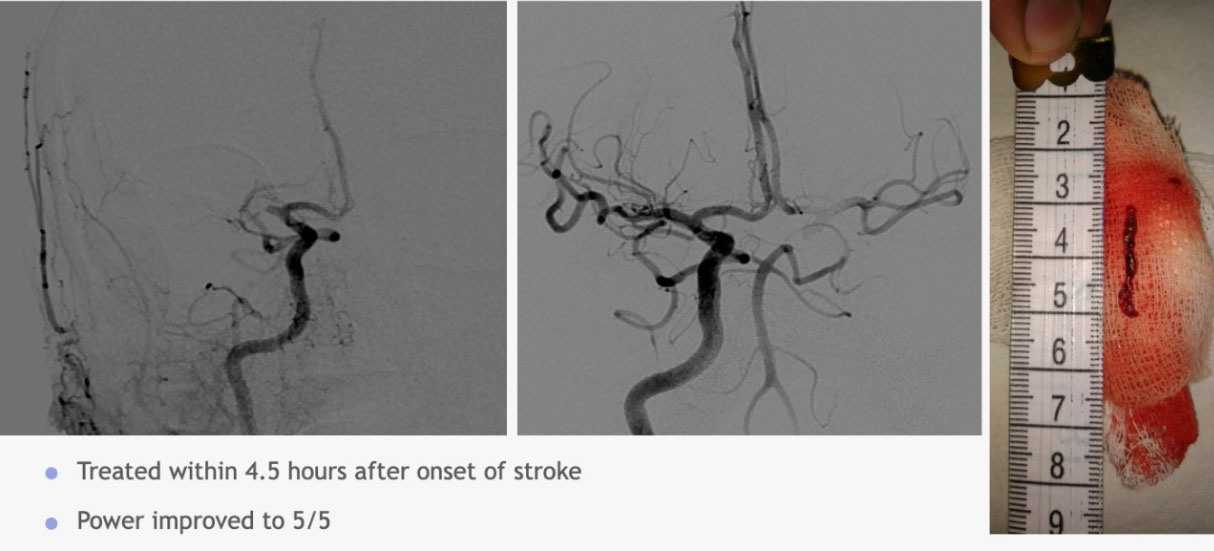

dr vivek ukirde 1214×551

dr vivek ukirde